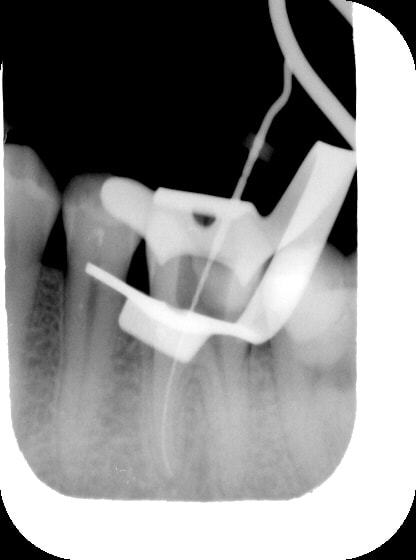

dedicace pour damdam ;)

mon endo du jour...

tech: reconstruction de la dent avant endo au fuji IX, pose de la digue, hypo camérale, laser Dmed caméral, lime 8, 10, 15, 20, 25 manuelles puis protaper jusqu'à F2, le tout sous loc d' apex et glyde, puis hypo-laser fibre 200m C+ en remontant, pointe de papier sterile 6%, laser pour secher, pate endo lentulo, laser en remontant, re-lentulo, maitre cone F2, laser grosse fibre G- sur les cones de gutta pour les rechauffer, fouloir pour condensation à chaud.... voilou, ma tech n a plus de secret pour vous.